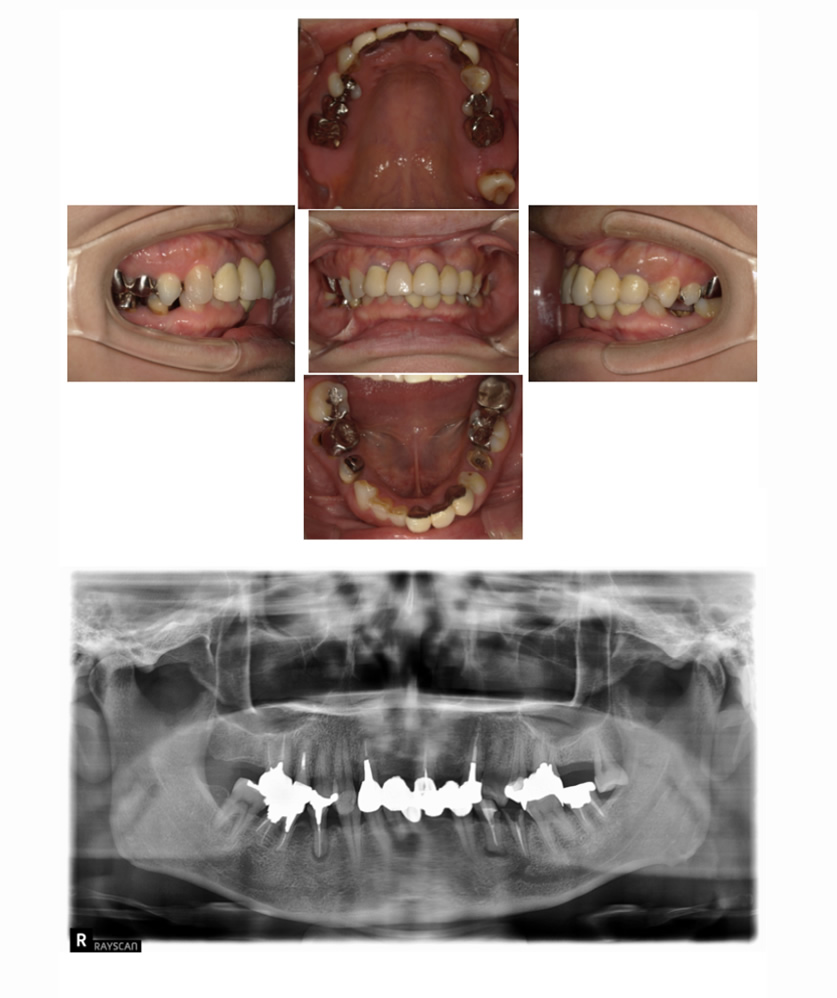

02 症例

歯の根の状態が悪いためインプラントにしたい

Before

After

| 治療内容 | 前歯の見た目が悪く、歯の根の状態も悪いのでインプラントにしたい。 |

| 患者様 | 50代女性 |

| 主訴 | 歯の根の状態が悪いためインプラントにしたい |

| 治療期間(目安) | 5ヶ月 |

| 治療費(税込:目安) | ¥2,702,700 (土台:5本、被せ物:7本) |

| リスク | 術後に多少の痛みや腫れが出ることがある。歯肉退縮がおきると、歯と歯肉の間に隙間が生じることがあります。 |